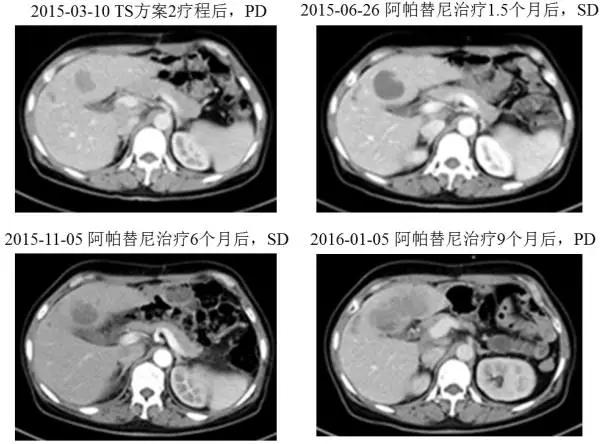

二线阿帕替尼单药

一线治疗对肿瘤控制情况不佳,于2015年4月改用阿帕替尼425mg poqd,3天后将剂量调整为850mg poqd。用药期间的不良反应主要为II度高血压,白细胞、血小板减少,I度腹泻,III度蛋白尿和双肩、膝关节疼痛。用药10天后,患者的AFP下降了37%,从56317降至35149ng/ml;1.5个月时AFP下降了74%,肝转移灶增大15%,CT值略降低,疗效评估为SD;3个月时AFP下降了75%,肝转移灶无变化,疗效评估为SD;6个月时AFP下降了84%,肝转移灶无变化,疗效评估仍为SD。

图3 患者阿帕替尼治疗前后的CT肝转移灶变化情况

患者于2015年11月开始出现大量蛋白尿(3-5g/24h),因此将阿帕替尼减量至425mg qd口服,但蛋白尿未见明显减少,遂停药2周(2015年12月17日至2016年1月5日),停药后蛋白尿降至0.72g/24h。2016年1月5日CT提示肝实质内大片状低密度病灶,较前增大110%。肠系膜区、腹膜后多发淋巴结,部分较前明显增大。AFP由7700升高至42000ng/ml。因此本次疗效评估为PD,二线阿帕替尼单药的TTP达到了9个月。